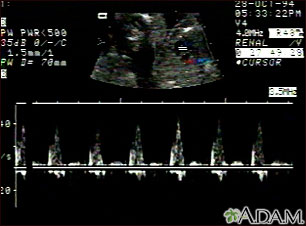

- Sometimes the PDA can be closed with a procedure that does not involve surgery. The procedure is most often done in a laboratory that uses x-rays. In this procedure, the interventional cardiologist makes a small cut in the groin. A wire and tube called a catheter is inserted into an artery in the leg and passed up to the heart. Then, a small metal coil or another device is passed through the catheter into the infant's ductus arteriosus artery. The coil or other device blocks the blood flow, and this corrects the problem.

- A newer method does not require surgery. An interventional cardiologist places a small wire through an artery in the groin and up to the aorta. A small balloon is then opened up in the narrow area of the aorta. A stent or small tube is left there to help keep the aorta open. The procedure is done in a laboratory with x-rays. This procedure is often used when the coarctation reoccurs after it has been fixed.